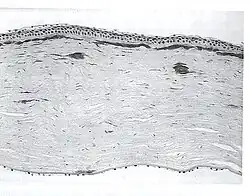

![]() Диаграмма джелсолина, демонстрирующая образование из него амилоидного белка вследствие мутации в кодоне 187 гена GSN | |

Амилоидоз финского типа — редкая форма амилоидоза, ассоциированная с геном джелсолина.[1] Отмечается потеря эластичности кожи, атаксия. Частью клинической картины является решётчатая дистрофия роговицы II типа.